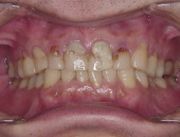

治療前のお口の状態です。むし歯や銀歯が見られます。

金属ではなく白い歯で、とのことでしたので、メタルフリーで治療方針を立てて患者様と相談し、進めていきました。

小さいものから、全部被せるものまでありましたが、ご希望通りの金属なしの治療を終了いたしました。患者様にもこの写真をお渡ししまして、比較をしていただきました。